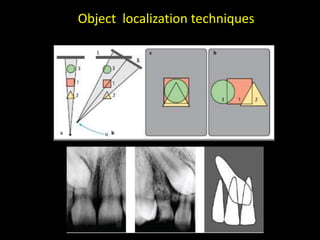

3. Special considerations for intra-oral radiography include techniques for mandibular third molars, gagging patients, endodontic procedures, edentulous ridges, and pediatric patients.